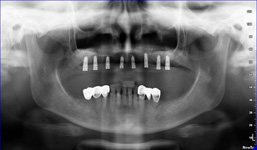

2) CB CT scan s modelem náhrady

8) Kontrolní RTG snímek po operaci